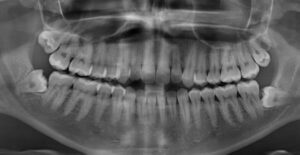

3. Yirmi Yaş Dişlerinin Sayısı Kişiden Kişiye Değişiyor

Bir, iki, üç veya dört adet yirmi yaş dişine sahip olabileceğiniz gibi, şanslıysanız bu dişlere hiç sahip olmamanız da mümkündür. Diğer bir olasılık ise, nadir de olsa, fazla diş adı verilen dörtten fazla yirmi yaş dişinin olmasıdır. Batı Virginia Üniversitesi Diş Hekimliği Fakültesi'nde klinik profesör yardımcısı Dr. William McCormick, bilgilerini şöyle aktarıyor;

"Kariyerimde hastaların dördüncü azı dişlerine sahip olduğu iki vaka gördüm. Atalarımız ise toplamda 12 yirmi yaş dişine sahipti."

McCormick'e göre, çene boyutu gibi genetik faktörler, bir kişinin sahip olduğu yirmi yaş dişlerinin sayısını belirliyor. Ayrıca ırk faktörü de bu sayıyı belirleyen şeylerden biri. Pratik olarak hiçbir Aborjin Tazmanyalının yirmi yaş dişi bulunmuyor. Yerli Meksikalıların neredeyse %100’ünde en az bir adet yirmi yaş dişi bulunuyor. Afrikalı Amerikalılar ve Asyalı Amerikalılar'da ise, Avrupa kökenli insanlara göre dörtten daha az yirmi yaş dişine sahip olma olasılığı daha yüksektir. Bu varyasyon, binlerce yıl önce ortaya çıkan ve böylece yirmi yaş dişlerinin oluşumunu engelleyen rastgele bir genetik mutasyona bağlanabilir. Bu mutasyon belirli popülasyonlarda daha yaygındır.